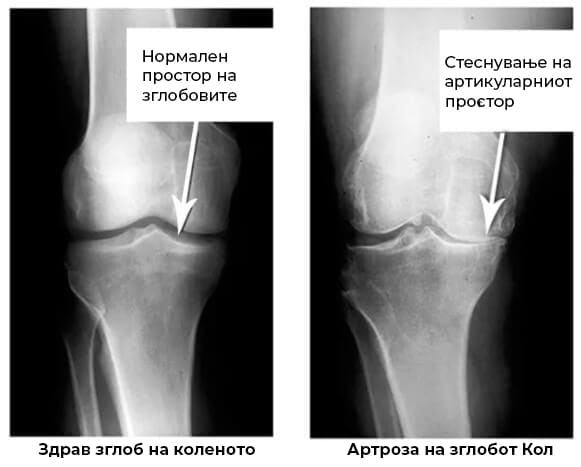

Погледнете ги овие снимки и ќе видите дека во првиот кадар нема зглоб простор, коските се тријат една со друга и тоа предизвикува силна болка. И тој процес е многу тешко да се запре!